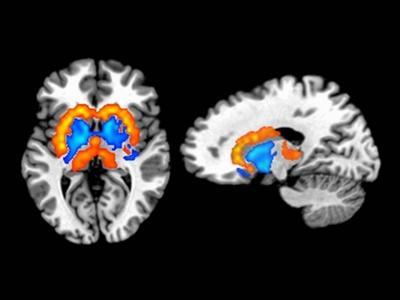

Dopamine signaling is thought to play a central role in orchestrating the processes of reward, motivation and habit formation. The depicted orange/yellow regions indicate where brain dopamine activity was positively related to obesity. These areas include the dorsolateral striatum which mediates the process of habit formation. The blue regions show where dopamine activity was negatively related to obesity and includes the ventromedial striatum, a brain region that controls reward and motivation.

(Photo Credit: Juen Guo, Ph.D. and W. Kyle Simmons, Ph.D.)